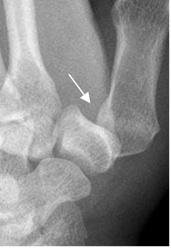

DEDO DEL ESQUIADOR O DEL GUARDABOSQUES:

Es ocasionado por trauma en abducción forzada de la articulación metacarpofalángica del pulgar, que produce esguince del ligamento colateral ulnar (1, 6).

En algunos casos se asocia con fractura por avulsión, sobre la base del 1º metacarpiano. (Fig 60).

Fig 60. Fractura del esquiador.

A y B: Rx oblicuas. Fracturas por avulsión en diferente grado, sobre la base de la falange proximal del 1º dedo, por lesión del esquiador.